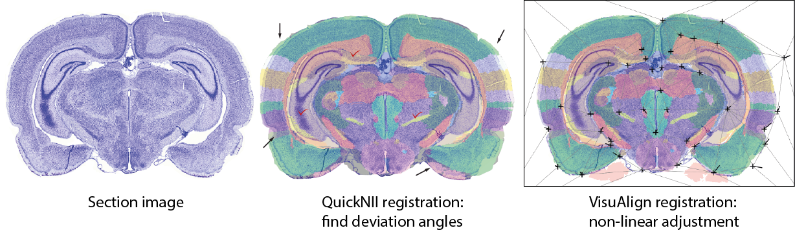

Tools for anatomical landmark based registration of mouse and rat 2D brain images to 3D reference atlases.

Histological data available on EBRAINS: DOI 10.25493/C63A-FEY Atlas shown in images: Waxholm Space Atlas of the Sprague Dawley Rat v.3 (Osen et al. 2019)